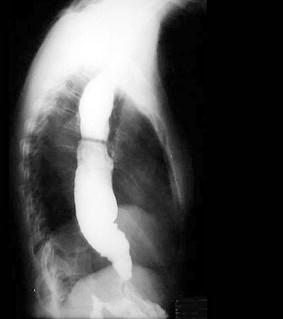

问题 患者,女性,45岁,10余年来常感咽下困难,胸骨后沉重感,症状时轻时重,自觉工作压力很大,X线钡餐检查结果如图所示,最有可能的诊断是 ( )

选项 A、食管平滑肌瘤 B、以上均不正确 C、食管憩室 D、贲门失弛缓症 E、食管癌

答案 D